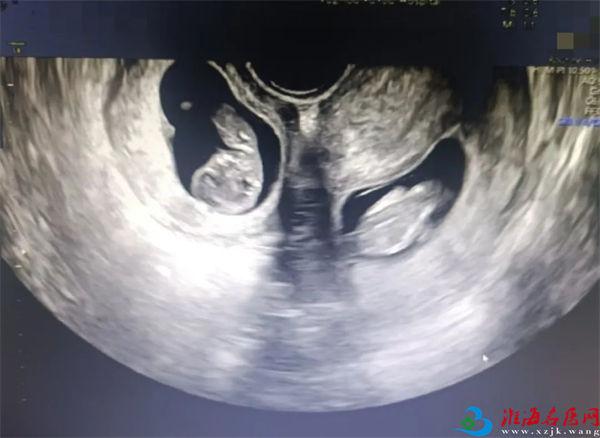

更令人意外的是,早孕期超声提示,晓晓腹中竟有两个胎儿,且两个孩子各居“一室”,互不干扰。“在我近30的职业生涯中,还从未遇到过双子宫双胞胎的孕妇。双子宫女性妊娠风险非常多,很可能会出现早产、胎儿生长受限、子宫破裂等情况,每种风险都不容小觑。”产科九病区主任吴惠莹如是说。

心形子宫 剖宫产术稳准快

7点50分,一场生命与时间的赛跑拉开序幕。与普通的双胎剖宫产手术不同,此次手术需要分别在晓晓的两个子宫上切口取出胎儿。

各科医护配合默契,主刀医生沙小龙手法娴熟,开腹、取子一气呵成。手术开始仅4分钟,伴随着一声清脆的啼哭,第一个孩子成功取出,女孩,1.6千克,2分钟后,男孩出生,体重2.03千克。

早早等在一旁的新生儿科医生立刻为两个孩子进行检查,随后转入新生儿病房进行救治。为了预防产后出血,取出龙凤胎后,沙小龙医生第一时间用药促进子宫及时收缩,两个子宫紧紧贴在一起,形成了一个完整的心型。